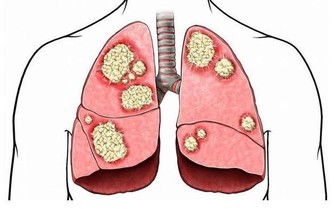

肺怕霧霾、煙氣刺激。中醫學認為,胸中為「上氣海」,丹田為「下氣海」,氣之所以能夠運行於全身,依賴肺氣的推動作用。

肺氣還能貫注於心血管,幫助心臟推動血液運行。

肺為「清虛之髒」,但霧霾、長期吸煙、二手煙不時傷害著它,

導致肺泡內痰飲積滯,阻塞氣道,清氣不能吸入,濁氣不能排出,上下氣海不流通,血液不能正常迴圈。

肺怕大便不通。中醫認為,肺和大腸經絡相通,關係密切。具體來說,大便通暢有利於肺氣下行。

比如小兒患肺炎時,如果大便不通,則熱毒不能下瀉排出,肺部的感染和咳喘會明顯加重。

所以治療時都會兼顧通導大便,以使病情減輕,病程縮短。平時宜多進食些芝麻、杏仁等食品,不僅能潤腸通便,還具有養肺利肺之功。